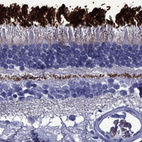

Immunohistochemical staining of human retina shows strong cytoplasmic positivity in rod outer segments.